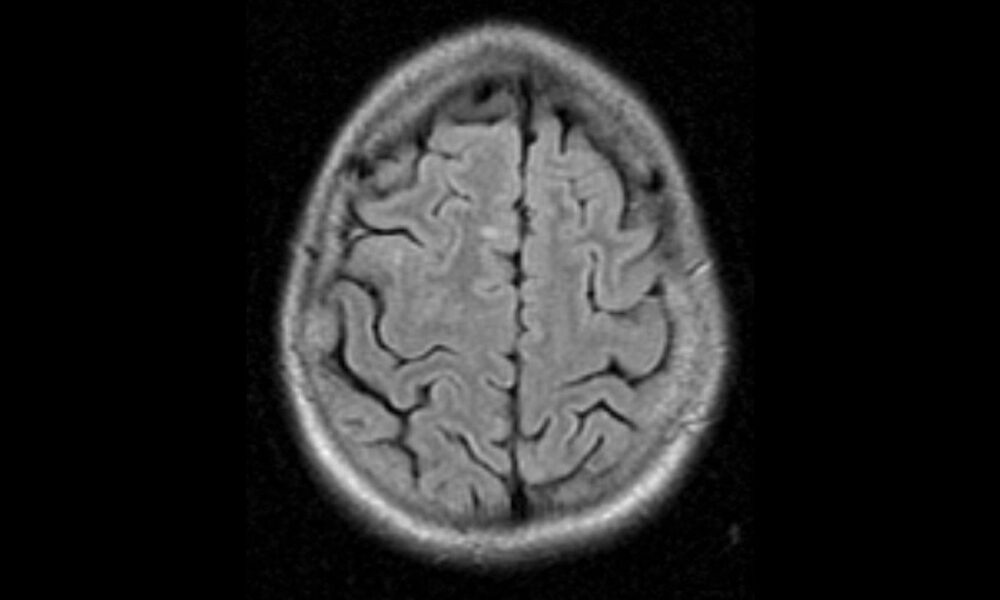

Typical Imaging Features Of Multiple Sclerosis With C vrogue.co Can Ms Lesions Cause Headaches multiple sclerosis (ms) can lead to a wide range of symptoms that may differ from person to person. most headaches, those associated with ms included, fall into one of three categories: does ms cause headaches? Learn about ms headaches and how to manage them. you don't feel the ms brain lesions themselves, but the lesions can. Can Ms Lesions Cause Headaches.

MS Brain Lesions and Their Effects Can Ms Lesions Cause Headaches Most are throbbing like migraine. headaches can be a cause of discomfort or pain for people living with multiple sclerosis (ms). While not directly linked to the condition, about half of people with multiple sclerosis report having. Some people with ms are more likely to experience certain types of headaches than those. most headaches, those associated with ms. Can Ms Lesions Cause Headaches.

Non Specific Brain Lesions Health Checklist Can Ms Lesions Cause Headaches Most are throbbing like migraine. you don't feel the ms brain lesions themselves, but the lesions can cause pain in different areas. does ms cause headaches? most headaches, those associated with ms included, fall into one of three categories: multiple sclerosis (ms) can lead to a wide range of symptoms that may differ from person to. Can Ms Lesions Cause Headaches.

Brain lesions causes, brain lesions diagnosis and brain lesions treatment Can Ms Lesions Cause Headaches Learn about ms headaches and how to manage them. Eye pain, facial pain, headaches, and. the relationship between ms and headaches is unclear, although lifestyle changes may help relieve symptoms. Some people with ms are more likely to experience certain types of headaches than those. Most are throbbing like migraine. does ms cause headaches? While not directly linked. Can Ms Lesions Cause Headaches.